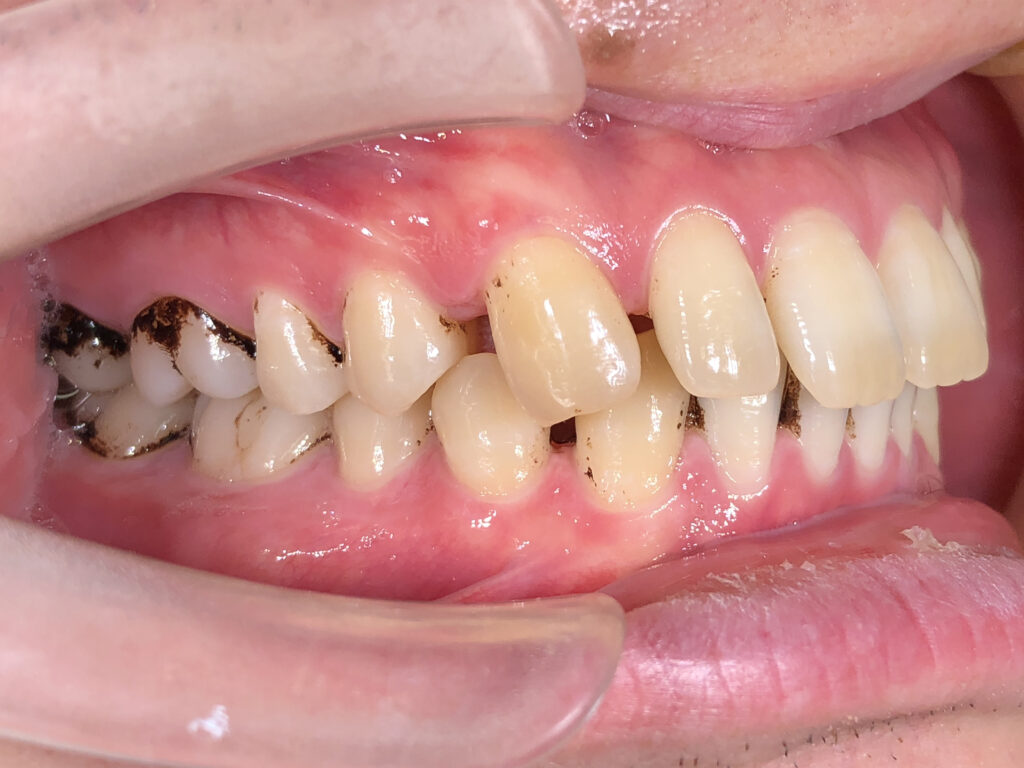

右側

治療前

患者様は上下の横の前歯の隙間を気にされており、「できれば完全に隙間を閉じたいが、ある程度改善されればよい」とのご希望で来院された。 インビザライン矯正では、前歯の近接移動を中心に計画し、効率的に隙間を閉鎖するため犬歯・小臼歯にアタッチメントを付与。また、閉鎖後の歯肉退縮やブラックトライアングルを最小限に抑えるため、歯根の平行性を意識して移動を行った。 治療により上下前歯の隙間は良好に閉鎖し、咬合も安定。審美的な改善とともに、発音や清掃性の向上にもつながった。 |